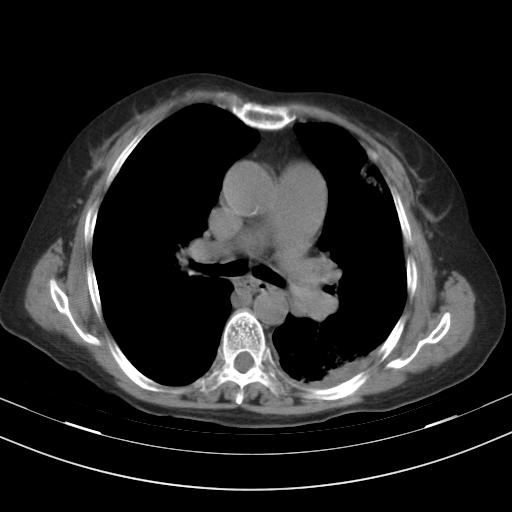

老年女性,嗜睡3天,意识模糊。轻咳,无发热。

两肺慢支炎伴感染,左侧胸腔积液。纵膈及双侧肺门淋巴结肿大建议复查。

1)两肺感染性病变;建议抗炎治疗后复查。2)纵隔淋巴结肿大。3)左侧胸腔积液。